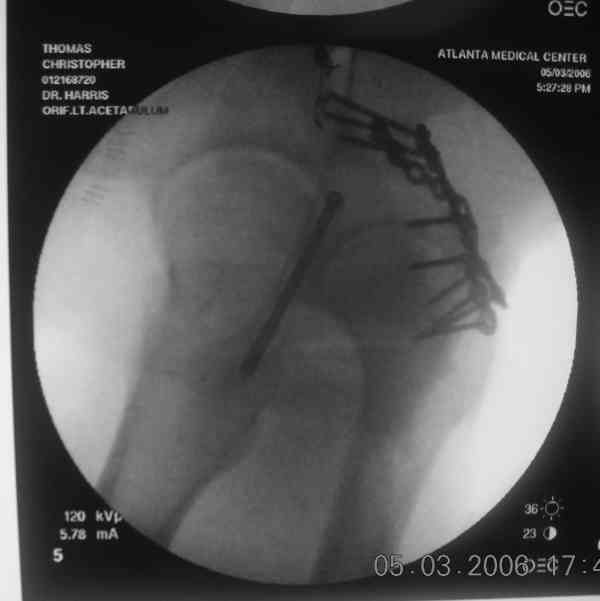

The 2nd example is of a motorcyclist with a transverse fracture-dislocation...he had a closed attempted reduction and placed in traction but the manipulative reduction was not concentric (not unusual for this injury pattern)...so the traction was adjusted to be just enough to disengage the head from the fracture (12#) until he could be cleared for surgery one day after injury...he was treated "urgently" then with a prone KL, clean the fracture, reduce and clamp it, screw it, support with a balanced plate, close, and enjoy...2-3hours, 400cc EBL, blah, blah, blah..

Prone

Here's a pic from the foot of the bed and you can see the clamp in the wound and the knee is extended so he must've had a tight rectus. The C-arm is rolled back to an obturator oblique image to reveal the anterior column...we put a slight outlet tilt to combine the images and give a better view of the anterior column...we can see the posterior column limb reduction in the wound, we can palpate the quadrilateral surface limb, and the image demonstrates the anterior column portion...you can adjust the tilt and rotation to image tangentially to the fracture plane if you'd like. We've inserted a 2mm K wire to site the starting point and aim/orientation for the drill and screw

Prone Imaging

same image, just another look.

Prone Inlet

OK, now we're inserting the drill percutaneosuy using a sleeve. This fluoro shot is not for this patient (notice no clamp) but I was too lazy to go searching the PACS for one with the clamp on, so pretend...I'll save the next ones and send along...the imaging is the same and the clamp doesn't obstruct imaging other than very rarely...you can always tilt the C-arm a bit to clear it if the clamp obstructs the exact spot that you'd like to see. We'll assume that everyone knows the safe zone for a medullary ramus screw. Use a calibrated drill and sleeve of known length to simplify your life...or use Alex's fancy cannulated screws...I like 3.5mm screws because the oscillating 2.5mm drill bounces and remains intraosseus when it oscillates and contacts endosteal cortical ramus... so will the screw, and like a long bent screw IF the fracture is clamped... if unclamped, when the screw contacts the endosteum, it pushes the reduction apart instead of bouncing. The big 7mm cannulated screws fit few patients and extrude...we very rarely use them any more...you'll see an old one later.

Prone Obturator-Outlet

Screw insertion using the obturator-outlet combination image.

12.Prone Obturator-Outlet

Same with a contoured pelvic reconstruction plate applied and tensioned.

Prone Iliac Oblique

The other oblique reveals the extra-articular implants.... you know the AC screw is extra-articular from the other views.

Routine Fixation

AC Screw

PC Neutr Plate

Others

The unstable caudal segment is secured by the lower 2 plate screws and the AC medullary screw... always assure that your fixation is sufficient to defeat the instability... part of your prop plan... but assure it before you close... it¹s your last chance... you shouldn't have to be pushing on the hip in contorted ways to determine your fixation stability...you can if that makes you 'comfortable'.